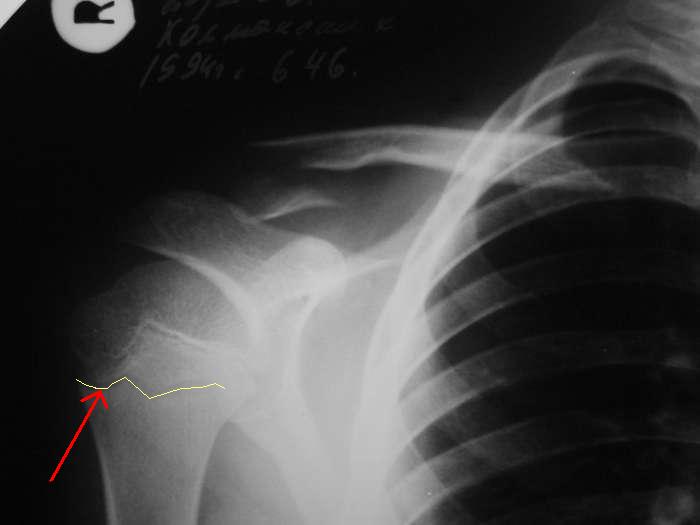

Александр, простите за настойчивость, на картинке я указал смутившую меня тень ... это вариант зоны роста?

> смутившую меня тень ... это вариант зоны роста?

Это контур зона роста на передней поверхности кости.

Перелома плеча нет, это зона роста с другой стороны кости.

По поводу проксимального плеча, согласен с вами, перелома нет - видна линия ростковой зоны.